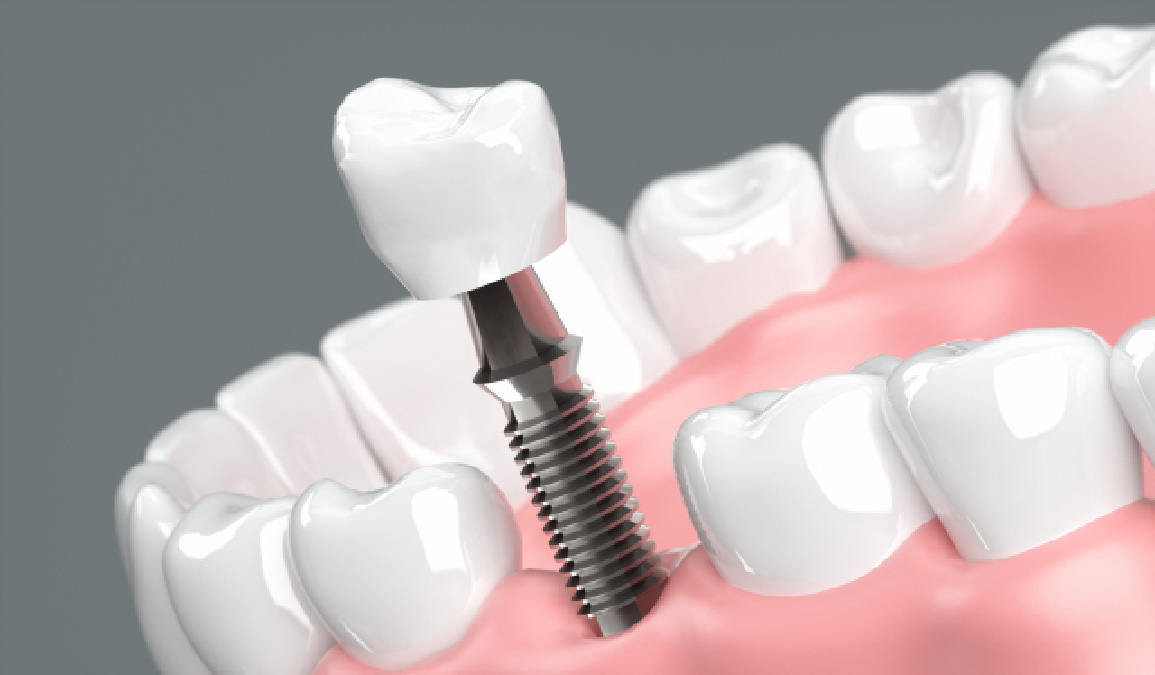

インプラントとは

インプラント治療とは、失ってしまった自分の歯の代わりに、人工の歯根を顎の骨に埋め込み、その上に人工の歯を作製して噛み合わせを回復する治療法です。

固定性であるためガタついたりせず、自分の歯のように噛めるようになります。慣れるまでは多少違和感を感じることもありますが、その期間を過ぎれば、自然の歯に匹敵する機能が得られます。最新の歯科技術によって、自分の歯と同じように作ることが可能です。